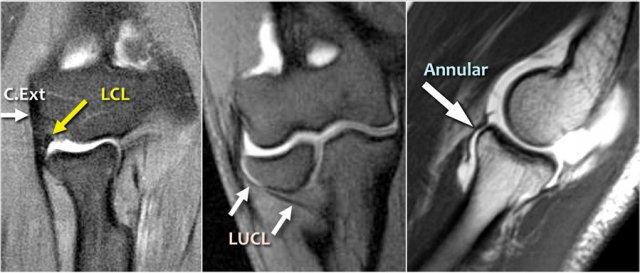

Lateral Collateral Ligament

Đây là hình minh họa về phức hợp dây chằng bên ngoài.

Nó bao gồm dây chằng bên quay, dây chằng bên trụ ngoài và dây chằng vòng.

Khi bạn tìm kiếm dây chằng bên quay, trước tiên hãy cố gắng xác định gân duỗi chung, vì ngay bên dưới nó bạn sẽ tìm thấy dây chằng bên quay (mũi tên vàng).

Khi bạn di chuyển về phía sau hơn, bạn sẽ thấy LUCL – dây chằng bên trụ ngoài, quét ra phía sau chỏm quay (mũi tên trắng).

Dây chằng vòng thường khó phân biệt với dây chằng bên quay (RCL), nhưng đôi khi có thể được xác định trên phim chụp MR-arthrogram theo mặt phẳng đứng dọc.

Common Extensor Tendon

Gân duỗi chung xuất phát từ mỏm trên lồi cầu ngoài.

Trên ảnh T1W, gân phải có tín hiệu thấp (mũi tên vàng).